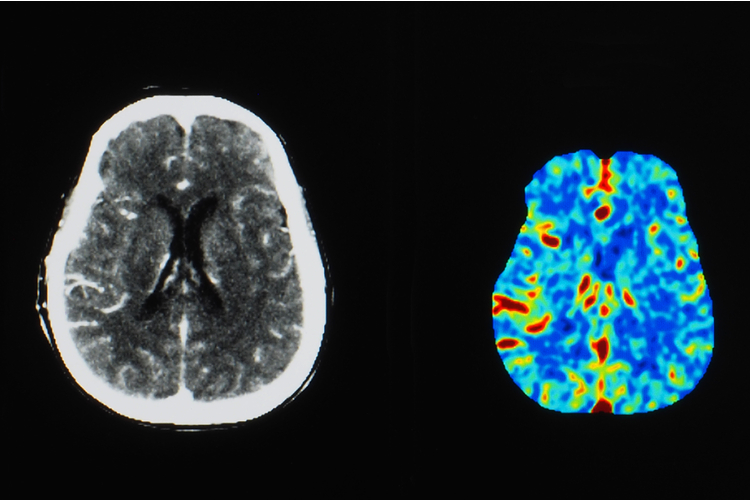

Ядрено-магнитният резонанс (ЯМР) с повишен контраст е често срещан вид диагностика; повече от 30 милиона процедури се извършват годишно в целия свят. Безопасността на контрастните вещества на базата на гадолиний (GBCA), които в момента се използват за такива ЯМР, наскоро беше поставена под въпрос.

Що се отнася до способността да се контрастира, учените я тестваха в проучване върху мишки. Експертите сравниха ефективността на новия контрастен агент Mn-PyC3A с два съвременни GBCA (Gd-DOTA и Gd-EOB-DTPA) при откриването на тумори при миши модел на рак на гърдата и метастатичен рак на черния дроб.